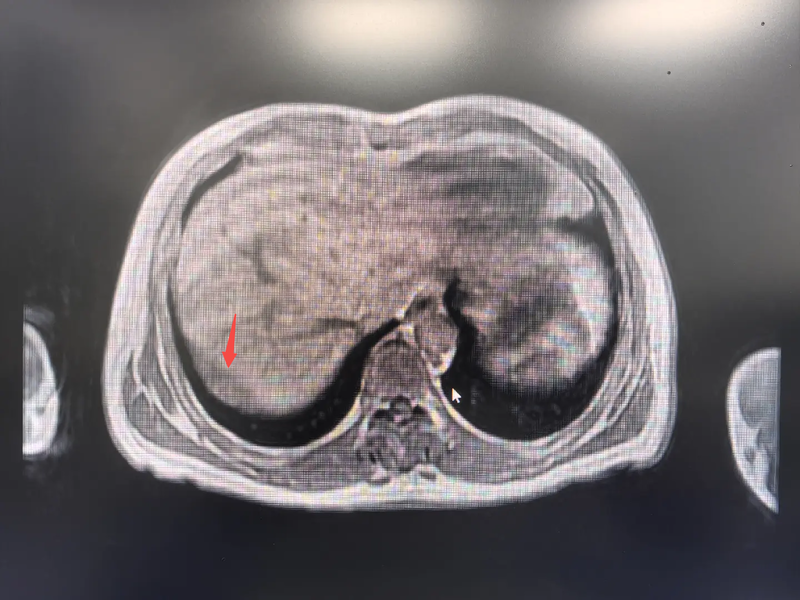

近期,李爷爷在体检中发现肿瘤标志物CEA升高,经全身PET/CT检查,发现其右膈下腹膜有一处新发病灶,糖代谢活性增高(提示肿瘤可能性大),且与肝右后叶包膜分界不清,临床考虑为腹膜转移性病变。

在游离肝周粘连后,团队不仅找到了预定的目标——那个约5cm*4cm的膈肌表面腹膜下的“炸弹”(术前发现的新病灶),还意外在肝脏上发现一个0.5cm的“小地雷”(术前没发现的微小病灶)。经现场讨论,团队决定将两个病灶一并切除。